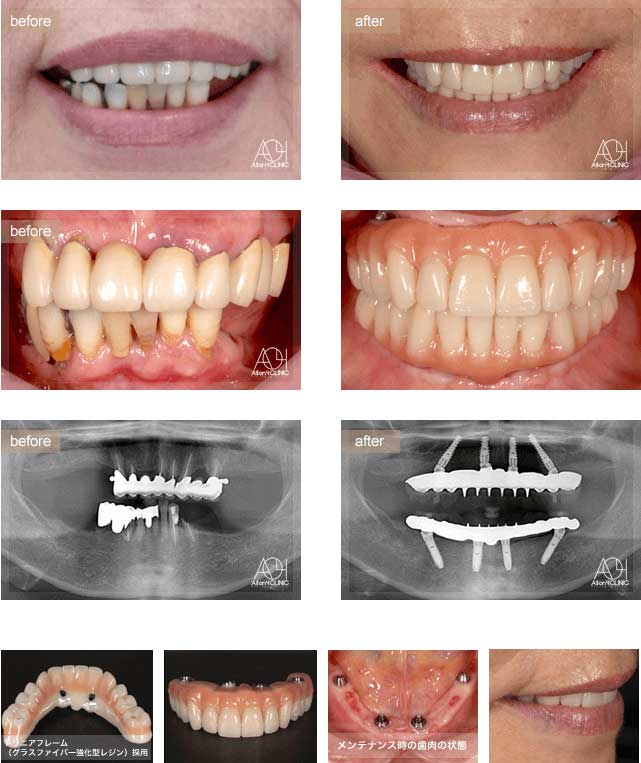

Treatment : All-on-4 zygoma

- Upper All-on-4

- Lower All-on-4

Age : 56 Sex : 男 S.T

| 主訴 | 仕事が忙しく歯には全く関心が無く、とうとう食事が困難になり治療を受ける事を決意。 |

| 治療内容 | ガイデッドサージェリーにてインプラント埋入。極めて骨量が少ないためザイゴマインプラントにて治療 |

| 治療費(総額) | ¥7,200,000(税抜)『モニター割引適用』 |

| リスク | 治療後の口腔管理が不適切な場合、埋入したインプラント周囲に感染・炎症を起こし、脱落する可能性がございます。 |